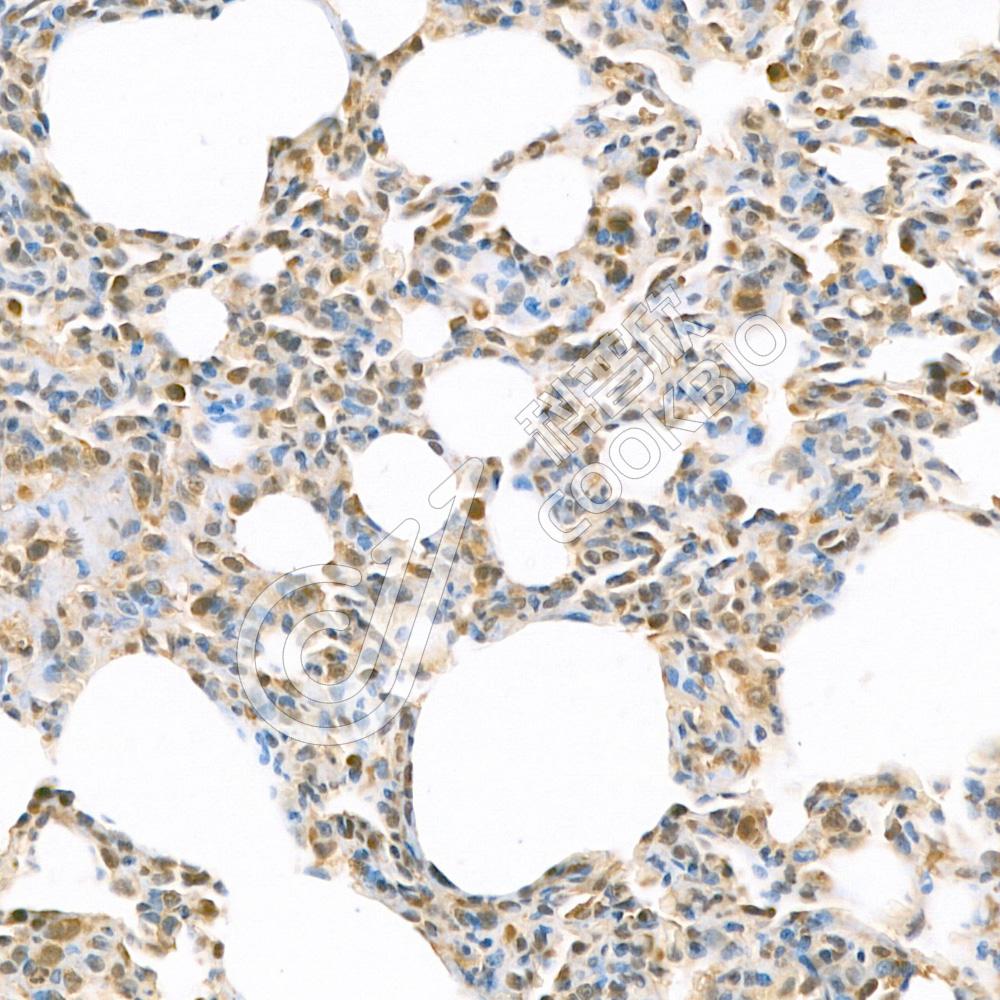

IHC检测IL-1 beta蛋白(货号 K133339).

样品: 小鼠损伤肺, 4%多聚甲醛 (货号KSG1101) 固定12-24小时.

抗原修复: 柠檬酸抗原修复液(干粉, pH 6.0) (KSG1201), 98℃, 20分钟.

—抗: 1: 1200稀释, 4℃ 孵育过夜.

二抗: S-vision免疫组化多聚二抗(山羊抗兔),即用型 (货号KB3906), 室温孵育20分钟.